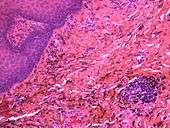

If necessary, the diagnosis can be confirmed histologically by excisional biopsy, which excludes nevi and melanomas.[3]:138 If a biopsy is taken, the histopathologic appearance is:[1]

- Pigmented fragments of metal within connective tissue

- Staining of reticulin fibers with silver salts

- A scattered arrangement of large, dark, solid fragments or a fine, black or dark brown granules

- Large particles may be surrounded by chronically inflamed fibrous tissue

- Smaller particles surrounded by more significant inflammation, which may be granulomatous or a mixture of lymphocytes and plasma cells